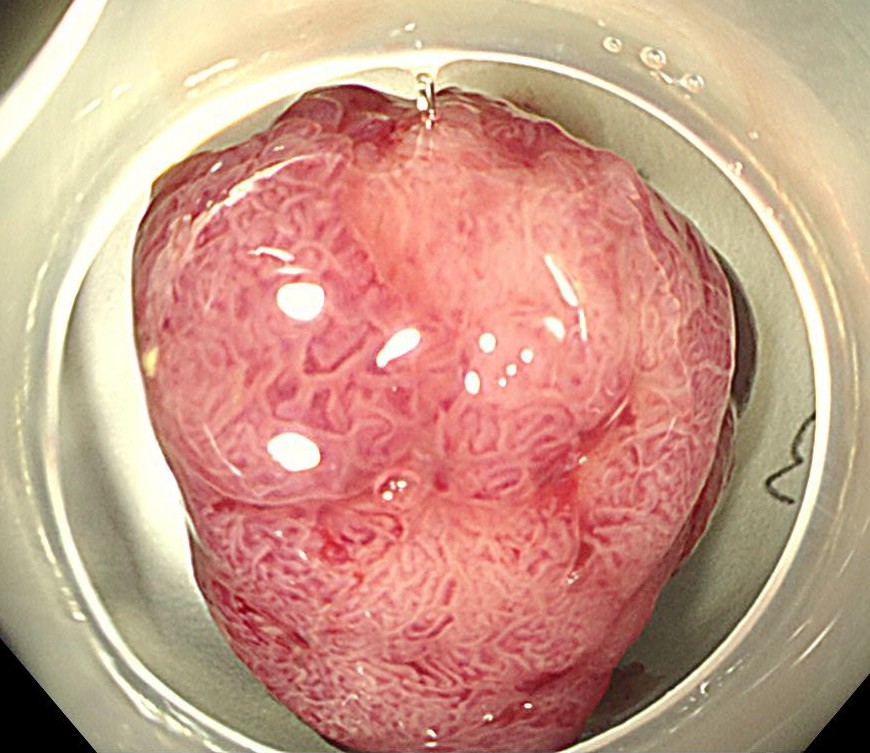

横行結腸に1型の腫瘍を認めます。

ピットパターンはおおむねIII型ですが、腫瘍基部と中心陥凹部はV型であり、早期の大腸がんが疑われます。